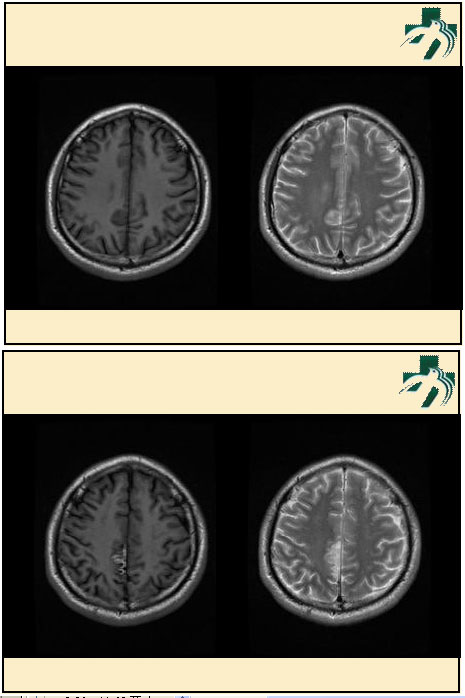

奴卡氏菌感染

第九期三博

读片会

病例之四

北京协和医院 提供

男性,22岁。自觉虫咬后皮疹、肢体麻木4月